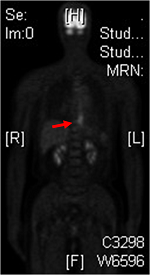

40´ë ¿©¼º¿¡¼­ ¹ß°ßµÈ Borrmann type IVÀÔ´Ï´Ù. ¼ö¼ú ÈÄ ÃÖÁ¾ º´¸®´Â ¾Æ·¡¿Í °°¾Ò½À´Ï´Ù.

- Histologic type : tubular adenocarcinoma, poorly differentiated

- Histologic type by Lauren : diffuse

- Size : 14x13x1 cm

- Depth of invasion : extension to subserosa (pT2b)

- Resection margin: free from carcinoma

- Lymph node metastasis : metastasis to 1 out of 47 regional lymph nodes

¼ö¼ú °á°ú¸¦ ¾Ë°í ´Ù½Ã ºÁµµ PET uptake°¡ ¾ø½À´Ï´Ù. Uterine myoma (È­»ìÇ¥)°¡ ¸Å¿ì ÇöÀúÈ÷ º¸ÀÌ´Â °Í°ú ºñ±³ÇØ º¸½Ê½Ã¿ä. ¿Â¸öÀÇ ¾ÏÀ» ÀüºÎ ¹ß°ßÇÑ´Ù°í ¾Ë·ÁÁø PET°¡ 14 cm±î¸® À§¾ÏÀ» ³õÃÆ´Ù´Ï irony°¡ ¾Æ´Ò ¼ö ¾ø½À´Ï´Ù.

PET ÆÇµ¶Áö¿¡ ÇÙÀÇÇÐ ±³¼ö´ÔÀº ÀÌ·¸°Ô ÁöÀûÇϰí ÀÖ¾ú½À´Ï´Ù. "Stomach¿¡´Â ¶Ñ·ÇÇÑ focal lesionÀÌ °üÂûµÇÁö ¾ÊÀ¸³ª signet ring cell cancer¿¡¼­´Â FDG ¼·Ãë°¡ ¶Ñ·ÇÇÏÁö ¾ÊÀ» ¼ö ÀÖÀ½".